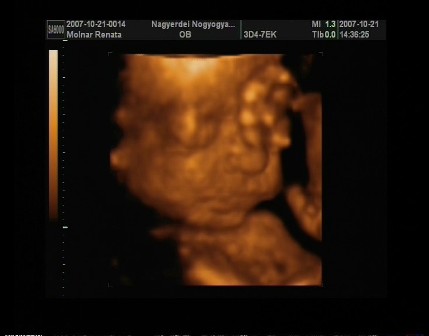

reni, na azt elhiszem hogy be vagytok már sózva az uh miatt!